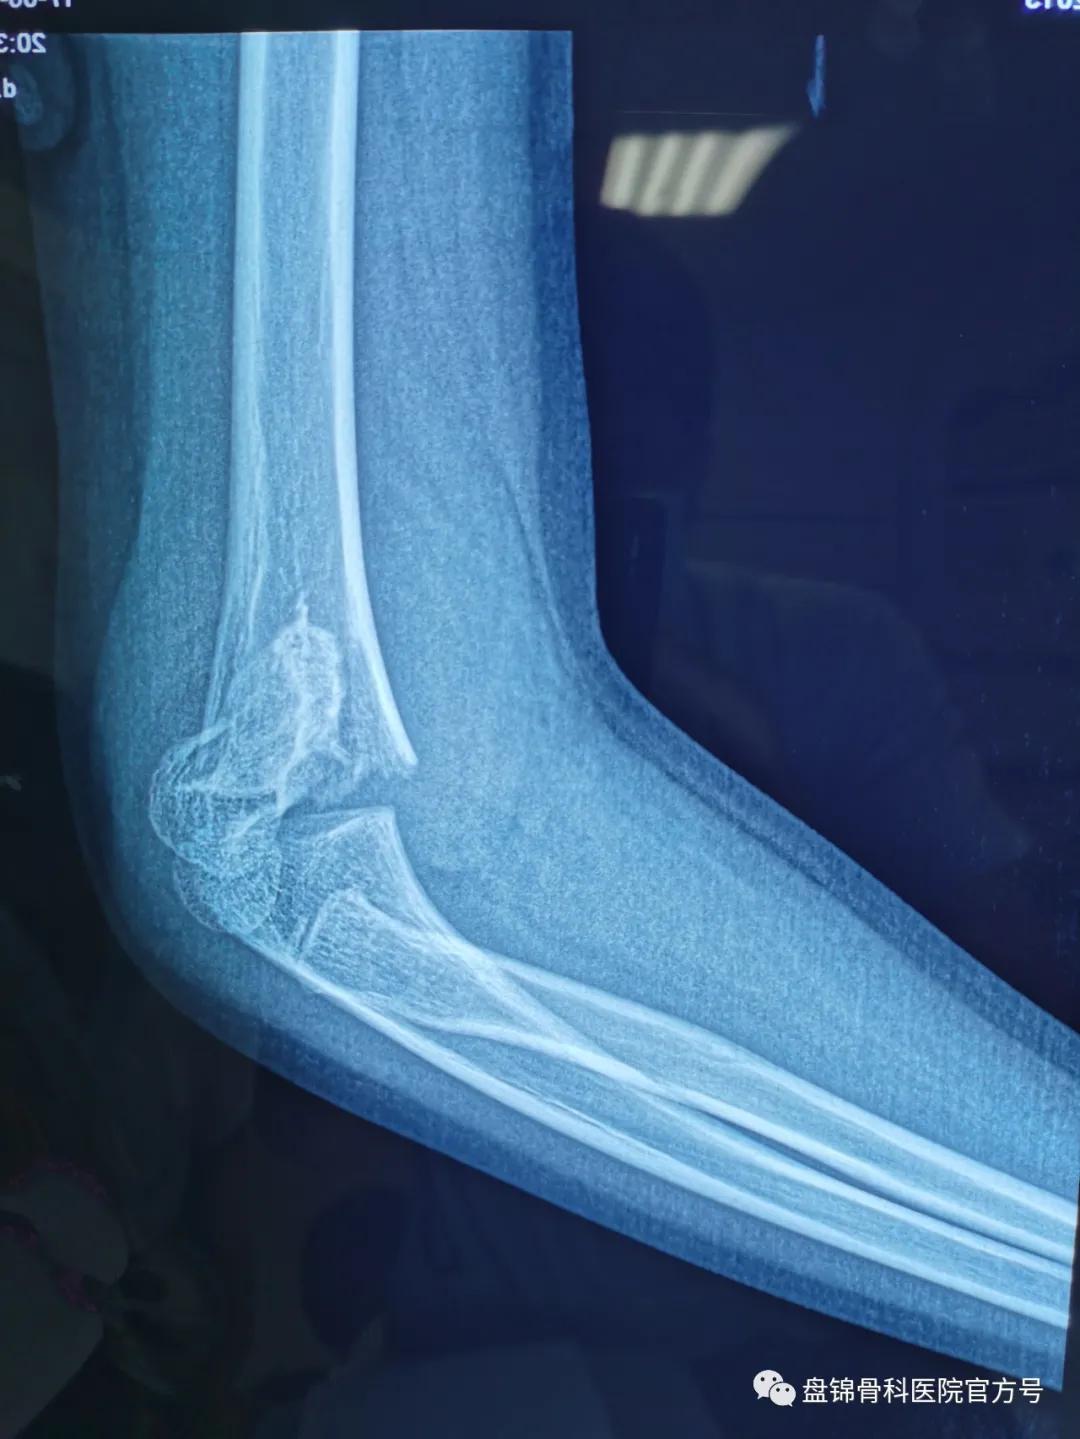

术前DR结果显示“右肱骨髁上骨折”

手足显微外科小儿病区袁钢主任第一时间查看患儿及阅片后跟家属交代, DR结果显示 “右肱骨髁上骨折” ,这种骨折应该手术治疗,可以行 右肱骨髁上骨折闭合复位克氏针内固定术。闭合复位克氏针内固定术可以解决手术切开治疗遗留伤疤,只留下针眼大小的伤疤,可早期活动关节,术后疼痛轻,恢复快。